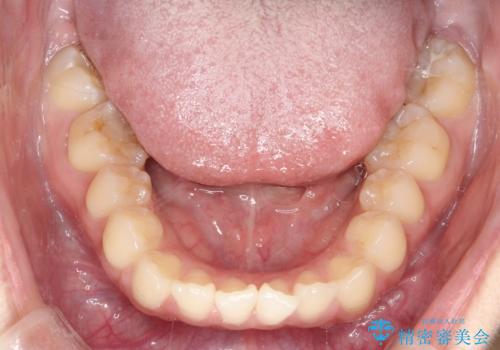

- 前歯の凸凹を主訴に来院されました。

予想治療期間2年でしたが、実際は1年半ほどで終了し満足していただきました。

小臼歯抜歯(上顎4番)して矯正治療を行なったことで、口元もスッキリしました。